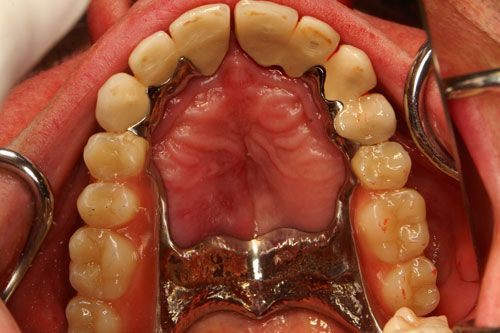

Ihr Zahnersatz wird größtenteils in unserem hauseigenen Labor von unserem erfahrenen Zahntechniker persönlich hergestellt, korrigiert und repariert. Wir setzen dabei auf modernste Technik und verwenden nur qualitativ hochwertige Materialien. Jeder Zahnersatz wird individuell in Farbe, Form und Material an Ihre Bedürfnisse angepasst. Das ermöglicht mit und meinem Team, Ihnen in kürzester Zeit eine finanzierbare, funktionelle und ästhetische Lösung anzubieten.